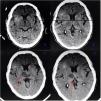

Este primer periodo transcurrió según el protocolo establecido, y se la extubó a las 4h de su llegada a la unidad, con retirada de medicación, débito por drenajes de 260ml en total y con buena diuresis. Sin embargo, en el primer día del PO en el horario matutino, la paciente, de forma abrupta y sin ninguna sintomatología ni signo clínico previo, presentó un cuadro consistente en desconexión del medio y entrada en coma, con necesidad de reintubación inmediata. Se realiza una tomografía axial computarizada (TAC) de cráneo que no informó de ningún hallazgo patológico, como se muestra en la figura 1. No obstante, debido a que el estado comatoso de la paciente no revertía, se hizo una interconsulta con el servicio de neurología y se decidió repetir la TAC a las 48h; en esta segunda TAC se objetivó el diagnóstico compatible con síndrome de Percheron (fig. 1).

Su presentación clínica se caracteriza por la afección del nivel de conciencia, incluido el coma, con cambios fluctuantes del mismo, así como alteración del lenguaje, del estado de ánimo, de los pares craneales, del movimiento, de la memoria (amnesia) y del sueño. De los escasos casos publicados, se ha visto que la principal causa de este síndrome (un 60%) es la enfermedad de pequeño vaso, y el otro casi 40% por cardioembolia, es más prevalente en el sexo masculino, con una edad media de presentación de 60 años, y relacionado en un 77% de los casos con factores de riesgo cardiovascular. La TAC inicial suele ser normal en la mayoría de los casos, y es necesario repetir dicha prueba o realizar una resonancia magnética, que el gold standard para su diagnóstico. En el caso que presentamos, fue la segunda TAC de cráneo la que confirmó la presencia del síndrome de Percheron. Al quinto día del PO, la paciente mantuvo un nivel de conciencia estable, lo que permitió su extubación, y quedó con una leve alteración de la memoria y claudicación de la extremidad superior izquierda, por lo que se la pudo trasladar a planta para continuar los cuidados, sobre todo rehabilitación1–4.